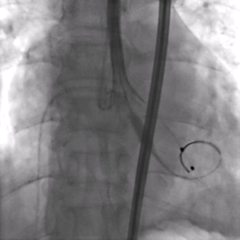

术前超声

超声提示:主动脉瓣右冠瓣脱垂,主动脉瓣中-重度关闭不全,左心系统扩大,二尖瓣少量反流。

造影及超声均可见主动脉瓣大量反流